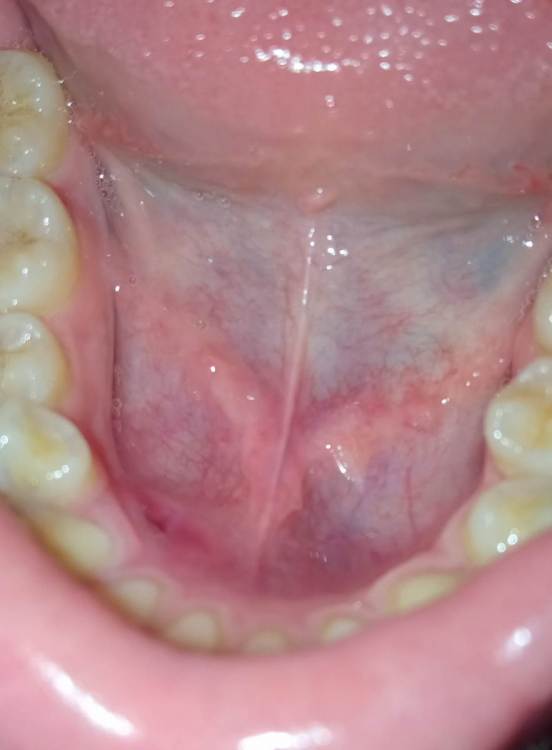

Faggott Опубликовано 6 августа, 2022 Поделиться Опубликовано 6 августа, 2022 28 июля мне поставили вот такую съёмную пластинку для расширения нижней челюсти: Ортодонт предупредил, что сначала будет дискомфортно, но нужно потерпеть, пока ротовая полость адаптируется. В первые дни всё было относительно нормально, а потом при каждом надевании, когда пластина нижним краем касалась мягких тканей под нижними передними зубами (в силу конструкции она всегда опускается вниз немного резко), чувствовалась боль. Я решила подождать адаптации, но с каждым днём надевать её становилось всё больнее и больнее (так как пластину нужно носить 22 часа в сутки, снимая только во время еды и чистки зубов, снимать и надевать её приходилось каждый день по 3 раза). При надевании было ощущение, будто бы меня бьют прямо по синяку, но через пару минут боль уходила. 3-4 дня назад на дне нижней челюсти (под нижними передними зубами) образовалось углубление, а сразу за ним бугорок, на вкус они были немного солёными. Однако больно мне было только пару минут после снятия/надевания пластинки. Сегодня вечером я обнаружила на месте углубления вот такую рану: Надеюсь, что к ортодонту попаду в понедельник. Стоит ли мне продолжать носить пластинку до понедельника? Во рту, кончено, всё очень быстро заживает, но если постоянно травмировать рану, то она, наверное, не заживёт. Нужно ли использовать какие-то препараты, кроме Хлоргексидина/Мирамистина? Ссылка на комментарий